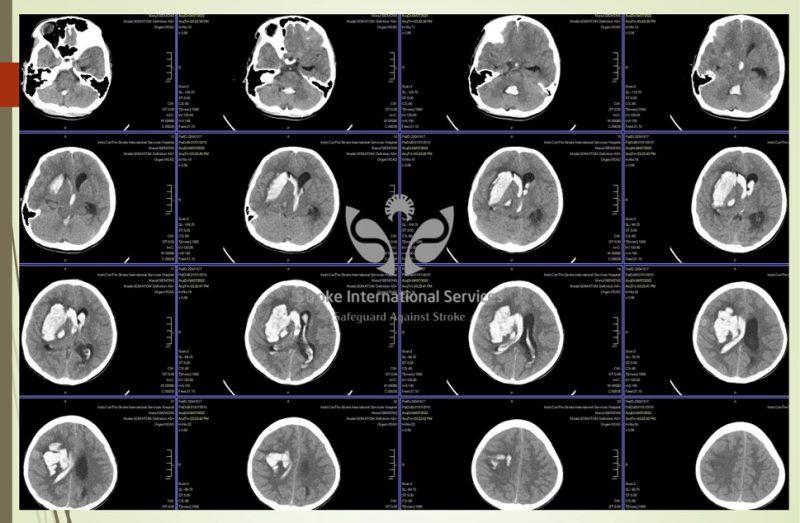

Hình ảnh xuất huyết não của bé 11 tuổi vừa được cấp cứu tối 7/4 tại Bệnh viện Đa khoa Quốc tế S.I.S Cần Thơ

Nhiều trường hợp trẻ em bị đột quỵ xuất huyết não, có dị dạng mạch máu não bẩm sinh, túi phình mạch máu não đã được đưa đến Bệnh viện Đa khoa Quốc tế S.I.S Cần Thơ trong thời gian gần đây, với triệu chứng khởi đầu là đau đầu, nôn ói, lừ đừ. TS.BS Trần Chí Cường – Giám đốc chuyên môn Bệnh viện S.I.S khuyến cáo: “Hãy cảnh giác với những cơn đau đầu đột ngột, kèm nôn ói, lừ đừ, tiếp xúc chậm chạp của trẻ em trong nhà! Đây là trường hợp bé 11 tuổi vừa được cấp cứu tối qua tại S.I.S Cần Thơ! Hiện còn đang nguy kịch.

Vỡ dị dạng mạch máu não là nguyên nhân phải nghĩ đến đầu tiên trong bệnh cảnh đột quỵ não trẻ em, khác hoàn toàn với đột quỵ người cao tuổi thường gặp tắc mạch gây nhồi máu não nhiều hơn. Đừng phí thời gian tự chữa tại nhà để tránh rủi ro cho các cháu, đôi khi còn mất luôn vĩnh viễn “cục vàng duy nhất của mình”… Với S.I.S không có gì khó trong việc chẩn đoán ngay nguyên nhân gây xuất huyết não trẻ em. Vấn đề khó nằm ở chỗ: lượng máu chảy? vị trí xuất huyết? tình trạng lâm sàng lúc nhập viện?… có còn cơ hội để cứu chữa cho các cháu hay không? Thời gian vẫn là yếu tố chúng ta có thể hi vọng và cũng đôi khi là tuyệt vọng không thể quay lại dù chỉ 1 phút giây! Xin các bậc phụ huynh chú ý: khi các cháu kêu đau đầu quá, nôn ói bất thường, lơ mơ, không linh hoạt như thường ngày, co giật, động kinh. yếu tay chân 1 bên… phải đi khám ngay. Việc chẩn đoán sớm được 1 dị dạng mạch máu não lúc chưa vỡ thì việc điều trị sẽ chủ động hoàn toàn và tất nhiên là an toàn hơn gấp 10 lần so với can thiệp lúc đã vỡ. Xin cám ơn các bệnh viện, các đồng nghiệp chuyên khoa nhi đã phối hợp rất tốt để cứu các cháu!”